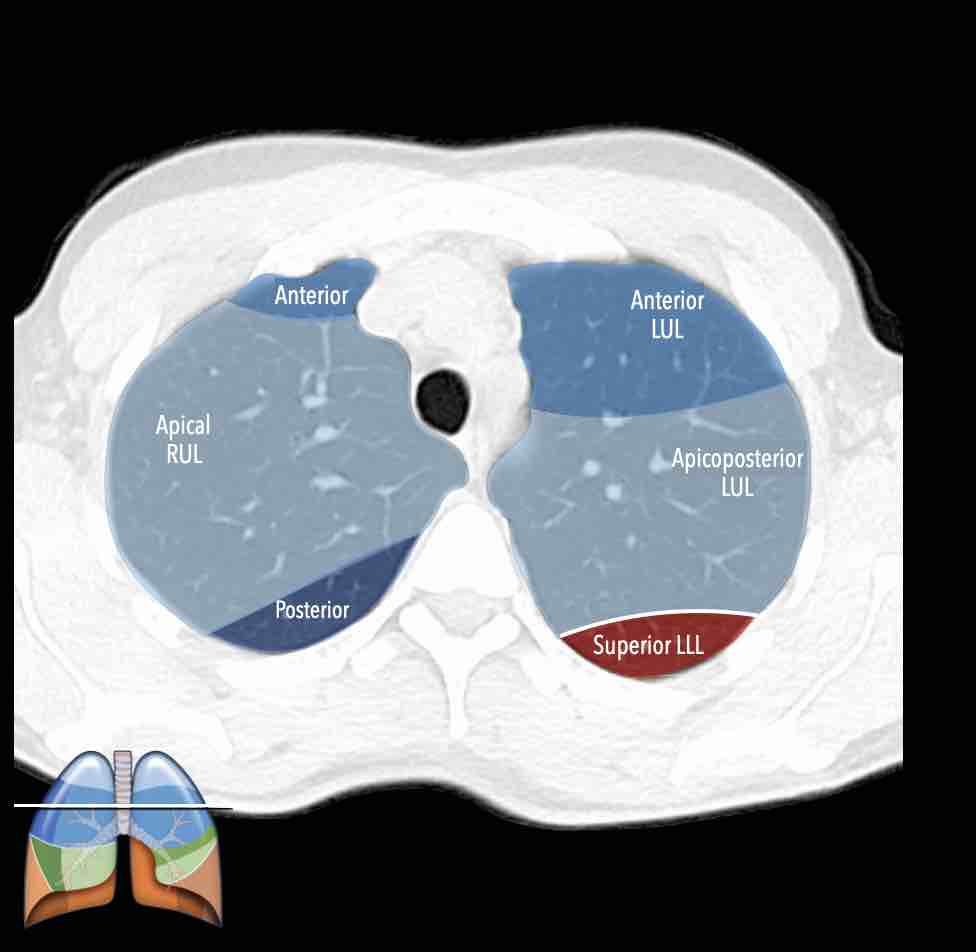

Các phân thùy phổi trên CT

Cuộn qua các hình ảnh để quan sát cách phổi được phân chia thành các phân thùy.